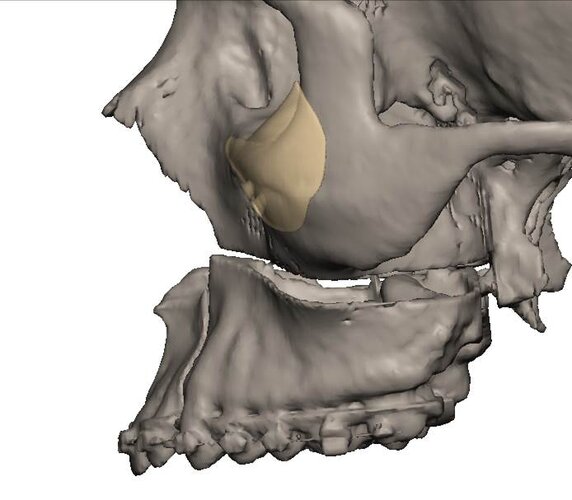

im getting surgery(trimax and infras) soon, any thoughts on this?my left side (the 31 mm) is also less wide in real life, i think would be good to extend it more to the nose area.